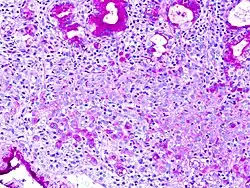

La técnica de Schiff es una reacción colorimétrica que se usa comúnmente en Histoquímica. Utiliza PAS, ácido peryódico de Schiff, o leucofucsina, un colorante incoloro, pero que se torna rojo estable al contacto con los grupos aldehídos.

La técnica de PAS se utiliza en el laboratorio dentro de los preparados para microscopía óptica, permitiendo la tinción de componentes celulares que contienen hidratos de carbono, por ejemplo algunas membranas celulares, células caliciformes en la mucosa del intestino, fibras reticulares que están rodeados por hidratos de carbono, etc. Entonces en esta técnica, el ácido peryódico oxida a los grupos hidroxilo (–OH) de dos carbonos cercanos, formando de esta manera grupos aldehídos compuestos por carbono, oxígeno e hidrógeno. Así la leucofucsina puede reaccionar con estos y dejar una tinción rojiza.

Esta técnica se usa en la tinción de estructuras que contengan una alta proporción de macromoléculas de hidratos de carbono, glicógeno, glicoproteína, proteoglicano, típicas por ejemplo del tejido conjuntivo, moco, glicocálix y lámina basal. También puede usarse para ayudar en el diagnóstico de varias enfermedades: